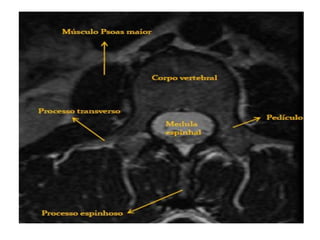

C3 a C7: Corpo, arco neural posterior,

lâmina, pedículos, processos transversos

e espinhosos.